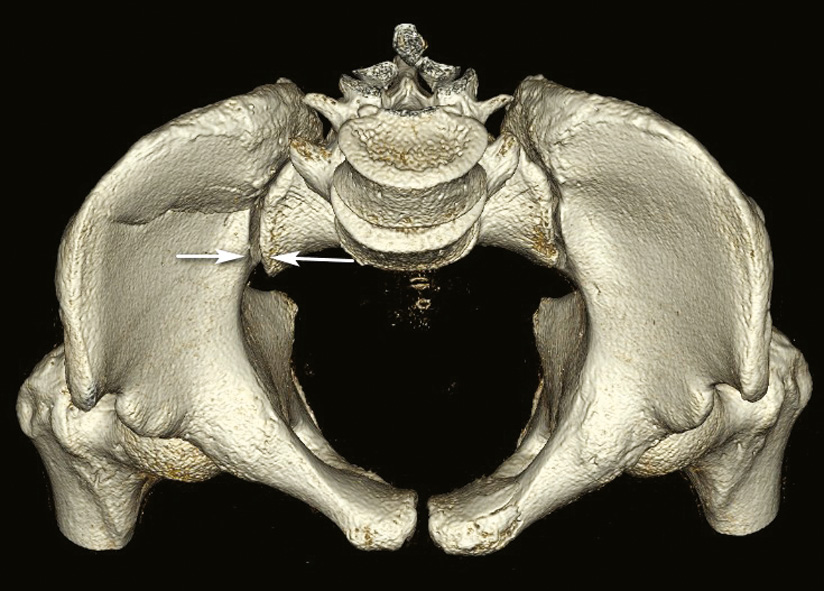

Calcar

The founder of acetabular surgery, E. Letournel, developed a classification for its fractures based on the two-column concept [14, 15]. The area of dense cancellous bone that participates in transferring axial loads from both columns of the acetabulum to the sacrum is referred to as the “sciatic buttress” (Fig. 11).

Fig. 11. Conditional localization of the sciatic buttress in the posterior iliac bone according to E. Letournel: a — outside view; b — scheme of the two-column concept of the acetabulum according to E. Letournel; 1 — anterior column; 2 — posterior column; 3 — sciatic buttress

It represents the area of the inferior posterior part of the iliac bone with the densest cancellous bone tissue, originating at the sacroiliac joint and extending further towards the acetabulum, forming the dome or arch of the greater sciatic notch. If, due to injury, there is a loss of connection between one of the columns and the axial skeleton through this bone region, it can be classified as either an anterior or posterior column fracture. In cases where both columnar connections to the axial skeleton are lost, it should be considered a two-column fracture of the acetabulum.

In the absence of a direct Russian equivalent in domestic literature, the term counterfort would be conceptually close, although it is primarily used in the context of describing cranial bones, such as the frontal-nasal or zygomatic counterfort [16]. However, an equivalent term with a similar meaning that has been used in trauma literature is calcar (for example, “calcar of the femoral neck” or “calcar of the shoulder). Given that this structure is located in the inferior part of the iliac bone, we propose the following term for its designation: “calcar of the iliac base”.